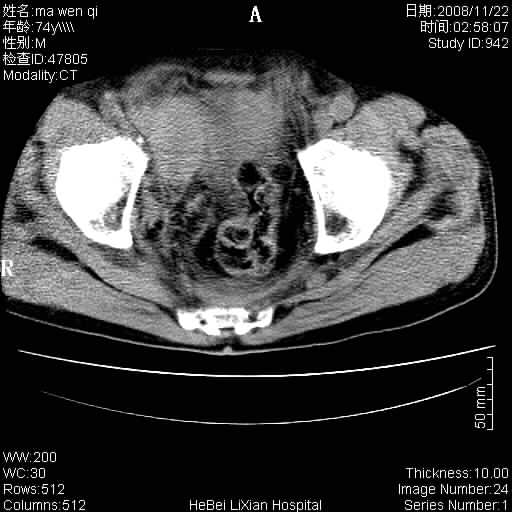

患者男 74岁.突然昏迷,休克6小时.血压70/30,头颅ct未见异常,既往体健.

补充病史,保留导尿10小时,尿袋内只有少许尿液,患者于住院后15小时后去世.

腹主动脉、双侧髂动脉夹层动脉瘤破裂出血进入腹腔。

考虑双侧髂a瘤,伴破裂出血

腹主动脉、双侧髂动脉夹层或动脉瘤破裂出血进入腹腔

1)考虑双侧髂动脉瘤并右侧动脉瘤破裂出血,右侧腹膜后及腹腔积血。2)双侧腹股沟疝。

支持(1)双侧髂动脉瘤并右侧动脉瘤破裂出血,右侧腹膜后及腹腔积血。(2)双侧腹股沟疝。

1)考虑,腹主动脉、双侧髂动脉夹层动脉瘤破裂伴右侧腹膜后及腹腔积血。2)双侧腹股沟疝。